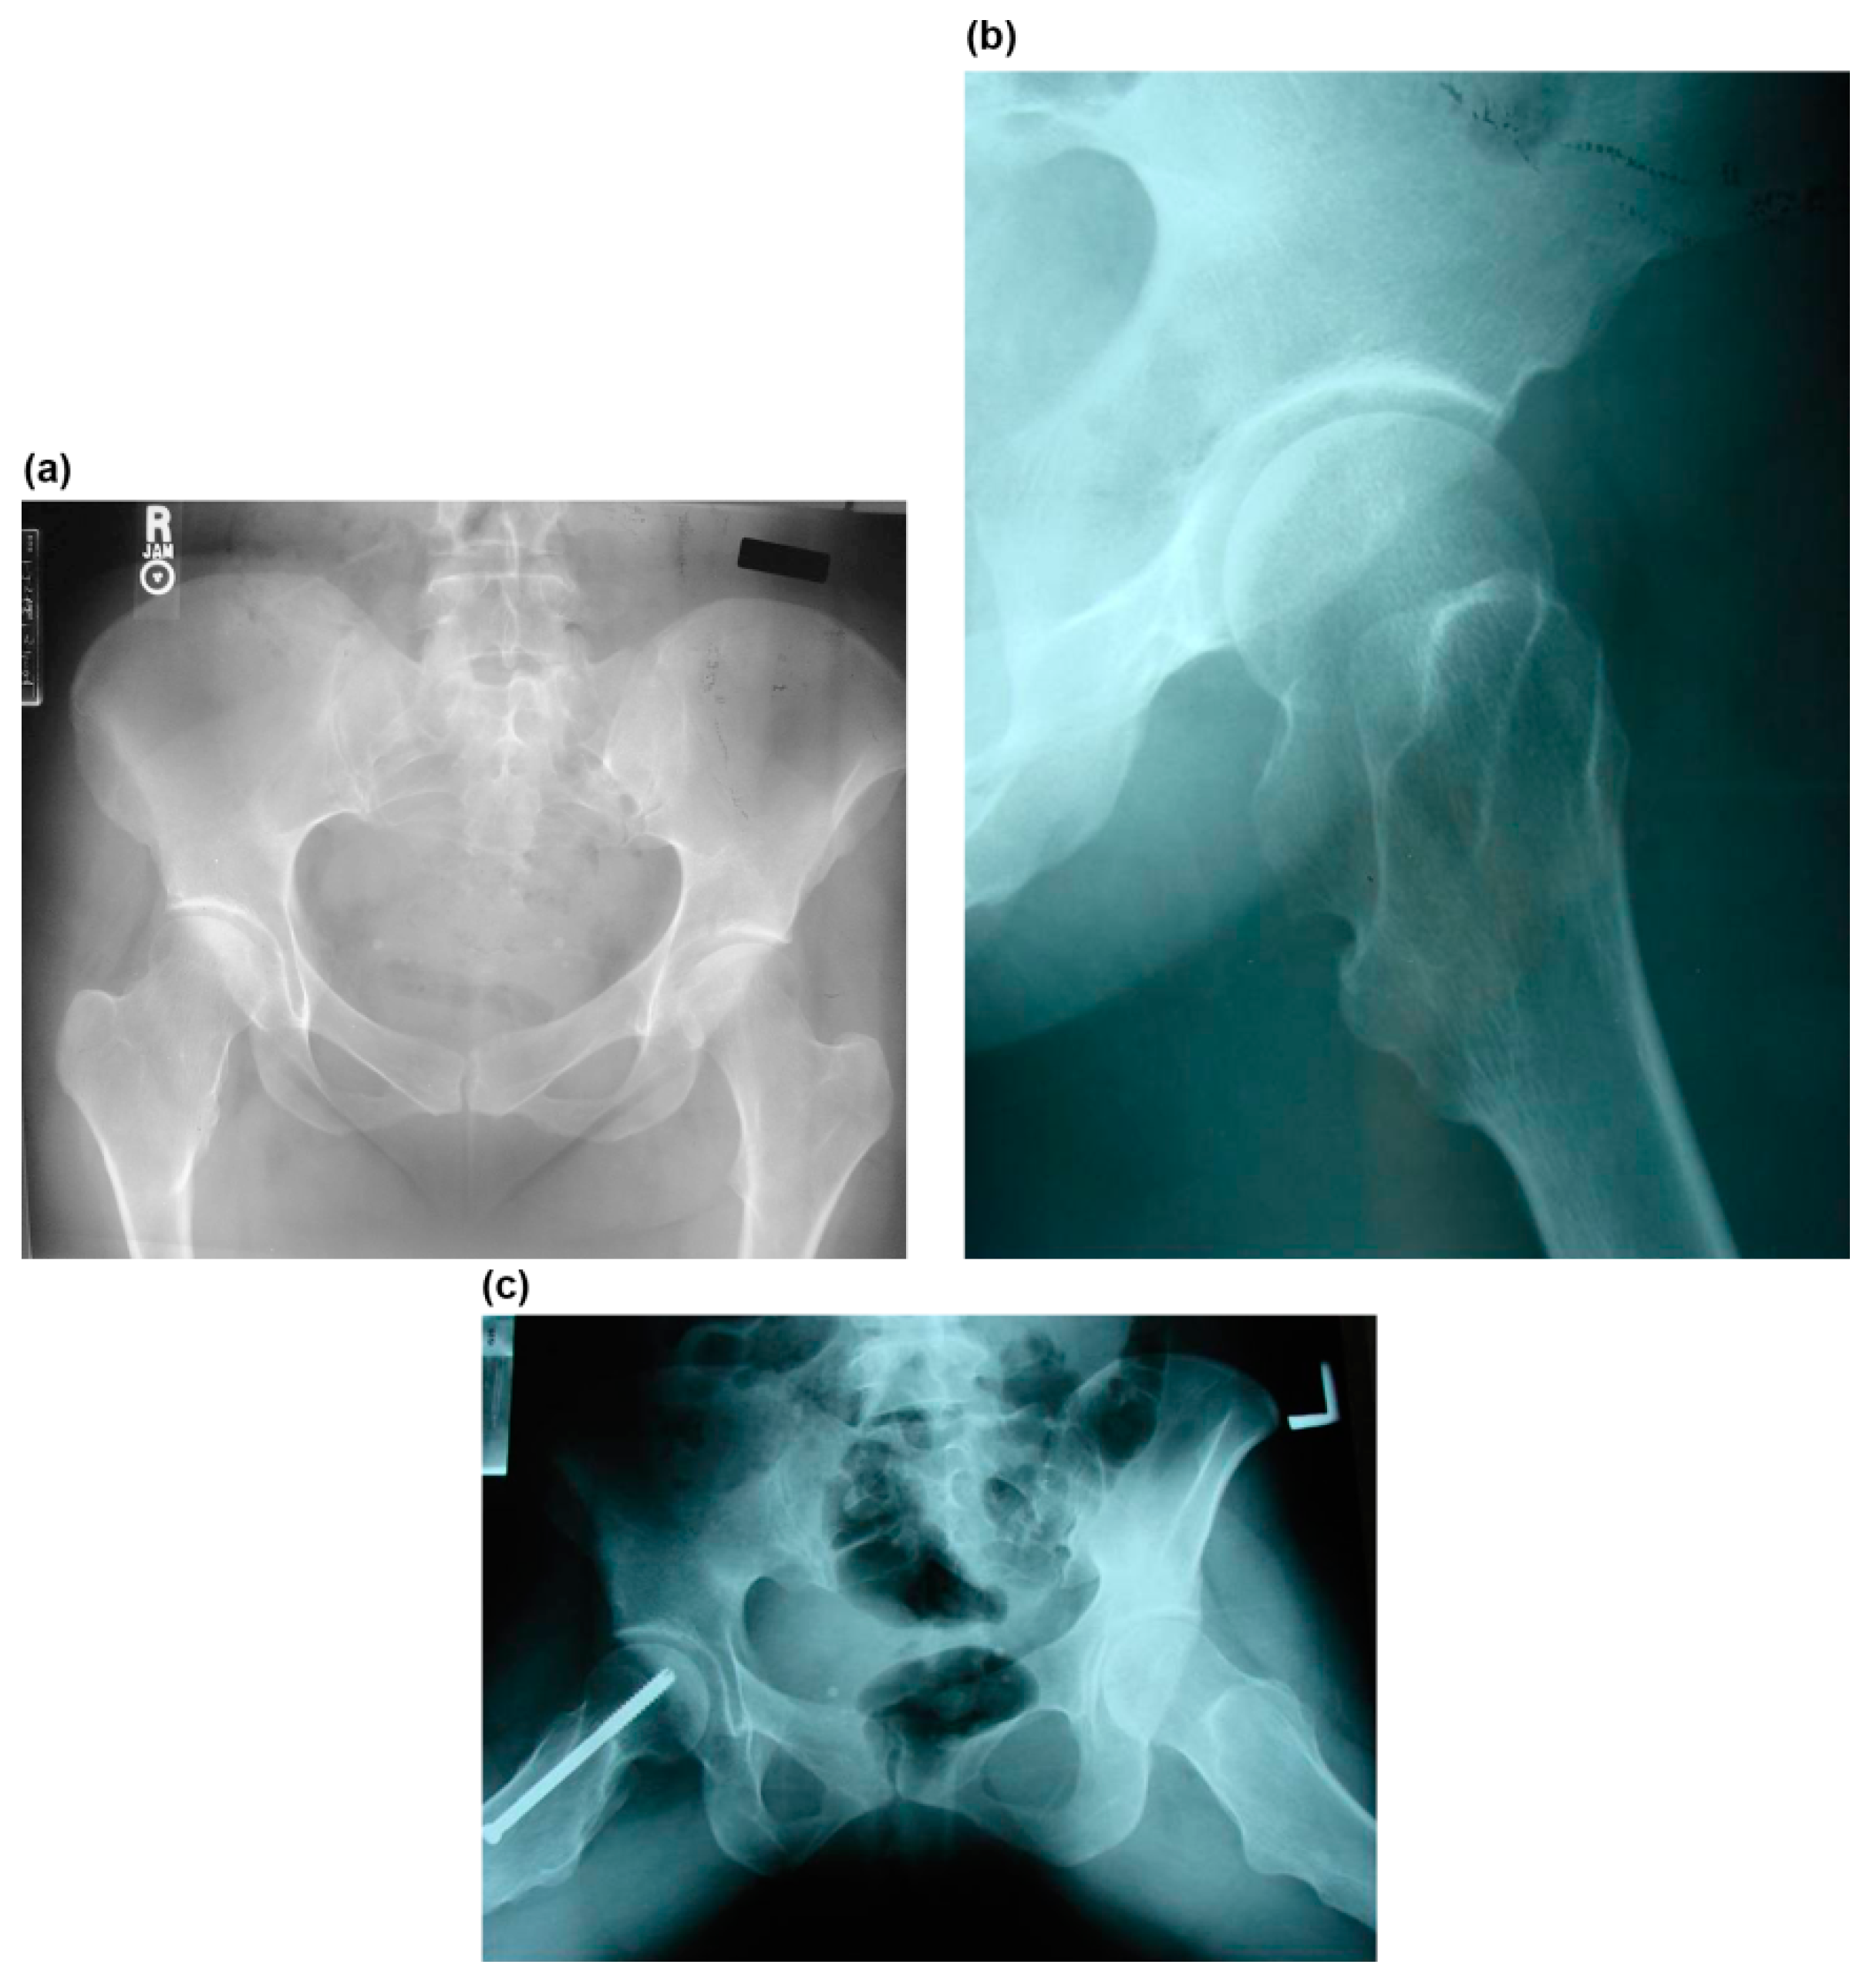

Figure 1.

A 14-year-old girl complained of posterior thigh pain at the right lower extremity that was aggravated with straight-leg raising (case no. 2). (a) Preoperative anteroposterior radiograph of the right hip shows a small bump at the medial side of the femoral neck. (b) Preoperative lateral radiograph of the right hip shows a large bump at the posterior side of the femoral neck. (c) The sciatica-like symptom was completely resolved after complete resection of the osteochondromas of the posterior femoral neck.